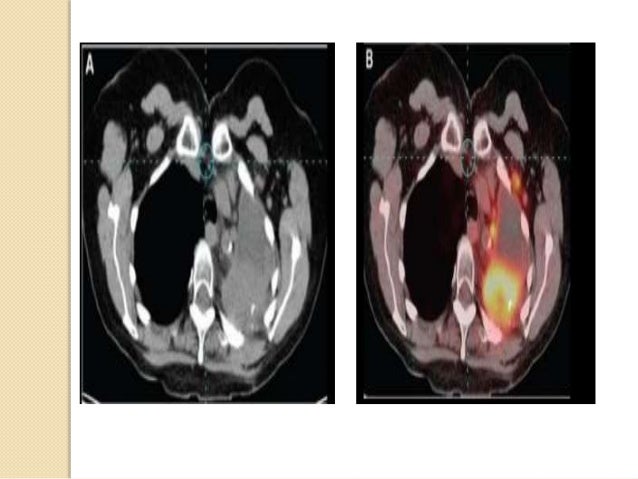

47. 47. Investigations II - Radiological: They include: 1. Chest X-Ray (CXR) 2. Node Ultrasonography (U/S) / Color Doppler U/S 3. Abdominal: U/S and CT 4. Throat culture/urethral or cervical swab for regional affection 5. Magnetic Resonance Imaging scans(MRI) 6. Positron Emission Tomography scans(PET)

54. 54. Investigations 4 - PET:  Most head and neck PET imaging is performed with the radio- labeled glucose analogue FDG Fluoro-Deoxy-Glucose which has increased uptake in viable malignant tumor due to enhanced glycolysis  The result can be expressed as a standardized uptake value (SUV), with those values > 2 being considered abnormal  PET scanning provides functional rather than anatomical imaging